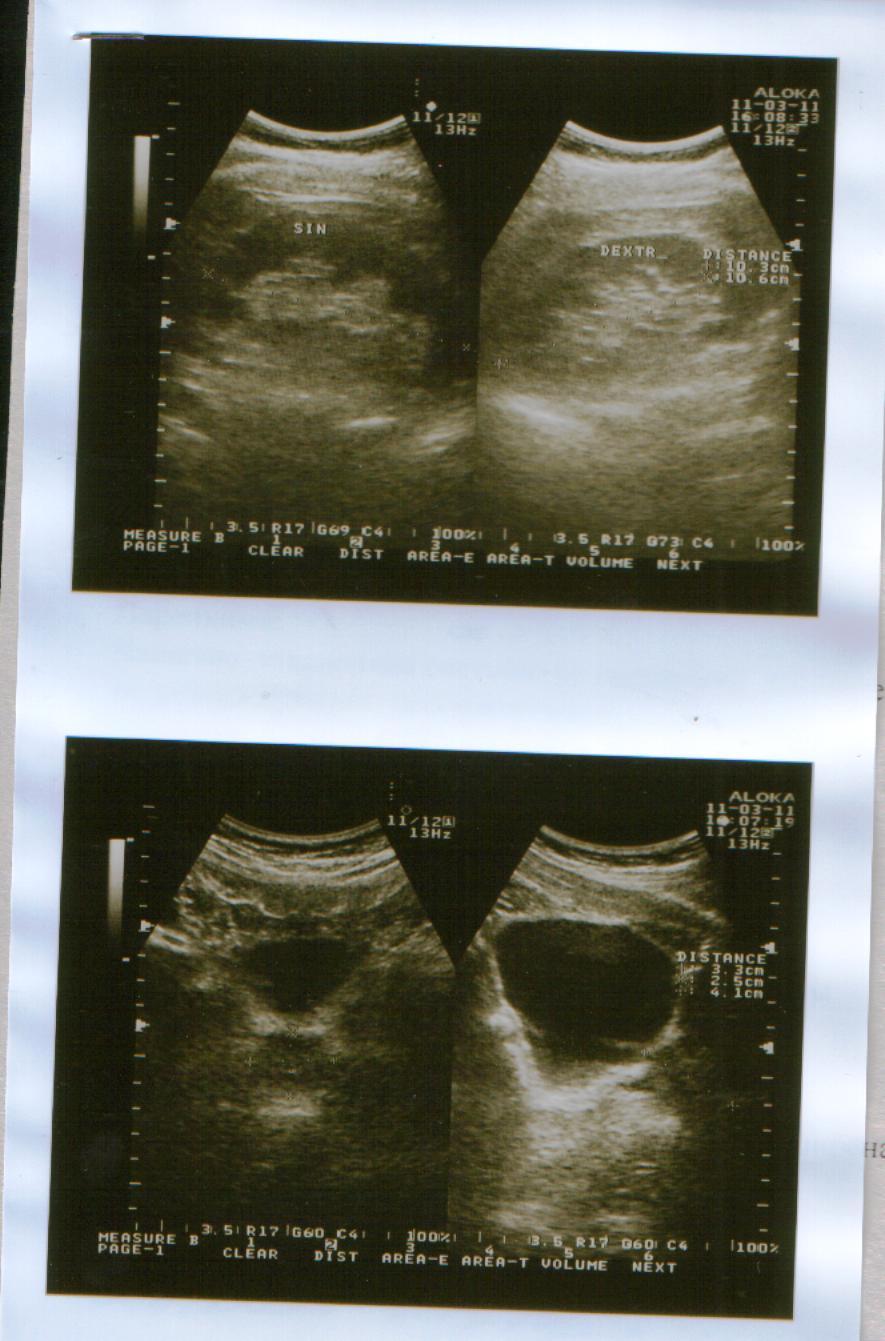

Сегодня(11.03.2011 г.)я ходил на приём к урологу.После осмотра он направил меня на УЗИ мошонки,простаты,мочевого пузыря и почек.УЗИ мошонки показало,что левое яичко действительно сжалось и почти в три раза меньше правого.Уролог сказал,что скорее всего,летняя операция грыжесечения и нынешняя проблема связаны и поставил мне диагноз "Атрофия левого яичка".А,да.УЗИ остальных органов показали,что всё остальное в порядке.Туберкулёза у меня не было и контактов с больными им тоже не было.

Снимки УЗИ и заключение уролога в прикреплённом архиве